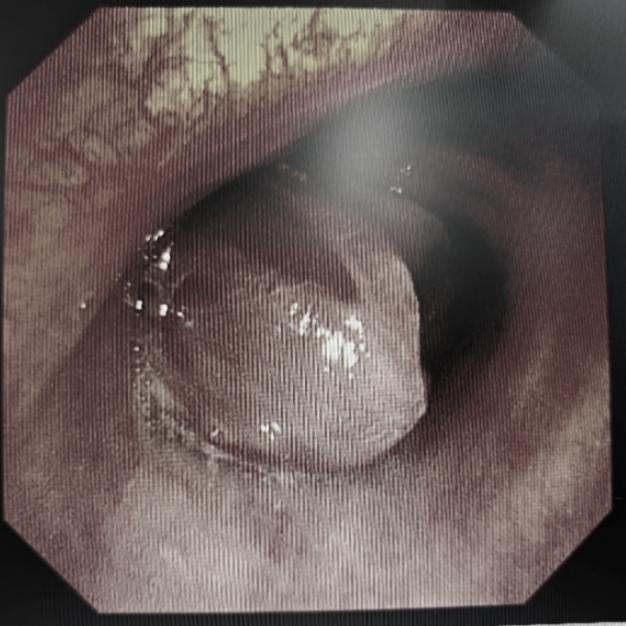

患者此前曾就诊于当地医院,行电子支气管镜检查提示“左主支气管隆起型病变,堵塞管腔,表面充血发红触之易出血,镜身难以通过。”当地医院难以处理,建议转诊到中国医科大学附属第一医院。

如前所料,第一个挑战就是麻醉。经麻醉医师精准操作,全麻气管插管后患者生命体征平稳,接麻醉机辅助通气,刘亭威操作软质气管镜顺利进入。镜下可见左主支气管新生物横跨气管隆突,向右主支气管生长,阻塞气管下段约70-80%,气管镜镜身小心通过,左主气道几乎被新生物完全堵塞。立刻使用电圈套器套切新生物,然而套切近根部时出血较多,患者血氧也一度降至70%。麻醉医生处乱不惊,立刻配合调整呼吸机参数,手术现场所有人都屏住了呼吸,眼神紧紧盯着连接气管镜的屏幕,术者刘亭威的额头也渗出了细密的汗珠,双臂和肩膀虽因长时间保持同一姿势而感到持续的酸痛,但持镜的双手却异常平稳,他立刻经鼻置入止血球囊,于左主支气管开口处压迫止血,同时经气管镜滴注稀释肾上腺素及血凝酶进行止血治疗,每一个动作都精准无误,有条不紊。出血很快止住,患者的血氧也恢复到了正常,生命体征恢复平稳。